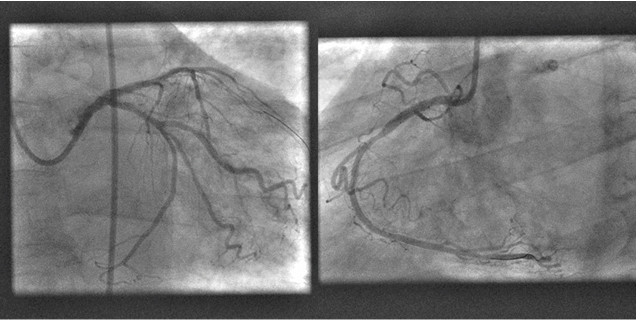

A 75-year-old male known to have Alzheimer’s disease and long-standing insulin-dependent diabetes mellitus. Present to our emergency room for three days history of altered general status, nausea and vomiting. Family state that the patient complains of a sub sternal progressive chest pain. Vital signs at presentation showed a blood pressure of 113/65 mmHg, heart rate of 98 bpm, tachypnea at 37/min. ABG showed: pH 6.9 (N 7.35-7.45), PO2 80 mmHg (N 65-105), PaCO2 19 mmHg (N 35-45), low bicarbonates 17 mEq/l (N 22-26 mEq/l), lactates 12 mmol/l. Other blood lab tests: elevated fasting blood glucose 480 mg/dl (N 72 to 99 mg/dl), normal potassium level at 3.9 mmol/l (N 3.5-5.0), elevated high sensitivity troponins at 642 ng/l, Pro BNP 2500 pg/ml, hemoglobin 12 g/dl, hepatic and renal functions were within normal limits, urine ketones were positive. The first ECG revealed large QRS complexes with a ventricular rate of 121, no ST-segment changes could be appreciated Figure 1, which is not related to potassium level changes. The diagnosis of late stage diabetic ketoacidosis was established and the patient was started on intravenous fluids and insulin. Intravenous sodium bicarbonate was also given and ECG was repeated few hours later which showed a normalization of QRS complex width, ST-segment elevation in the aVR > 2 mm, and ST depression in V3 to V6 and inferior leads. Figure 2 Transthoracic echocardiogram showed anterior, septum, apex, and inferior wall hypokinesia. The patient was taken to the Cath lab where coronary angiography showed 3-vessel disease with subtotal occlusion of left main coronary artery, second marginal and proximal right coronary artery. Figure 3 Left main and proximal right coronary arteries were stented successively with good results. Figure 4 The subsequent ECG showed complete ST segment resolution. Figure 5

Figure 4: Left Main and Proximal Right Coronary Arteries Were Stented Successively With Good Results